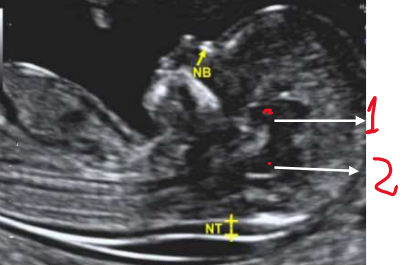

III - As estruturas assinaladas na imagem abaixo, correspondem ao diencéfalo (1) e ao tronco cerebral/ponte e bulbo (2).

II - A medida do CCN (comprimento cabeça-nádegas) deve estar entre 45-90 mm para

realização da avaliação morfológica do 1º trimestre.

IV - A imagem deve estar ampliada de maneira que apenas a cabeça e a parte superior do tórax sejam vistas.